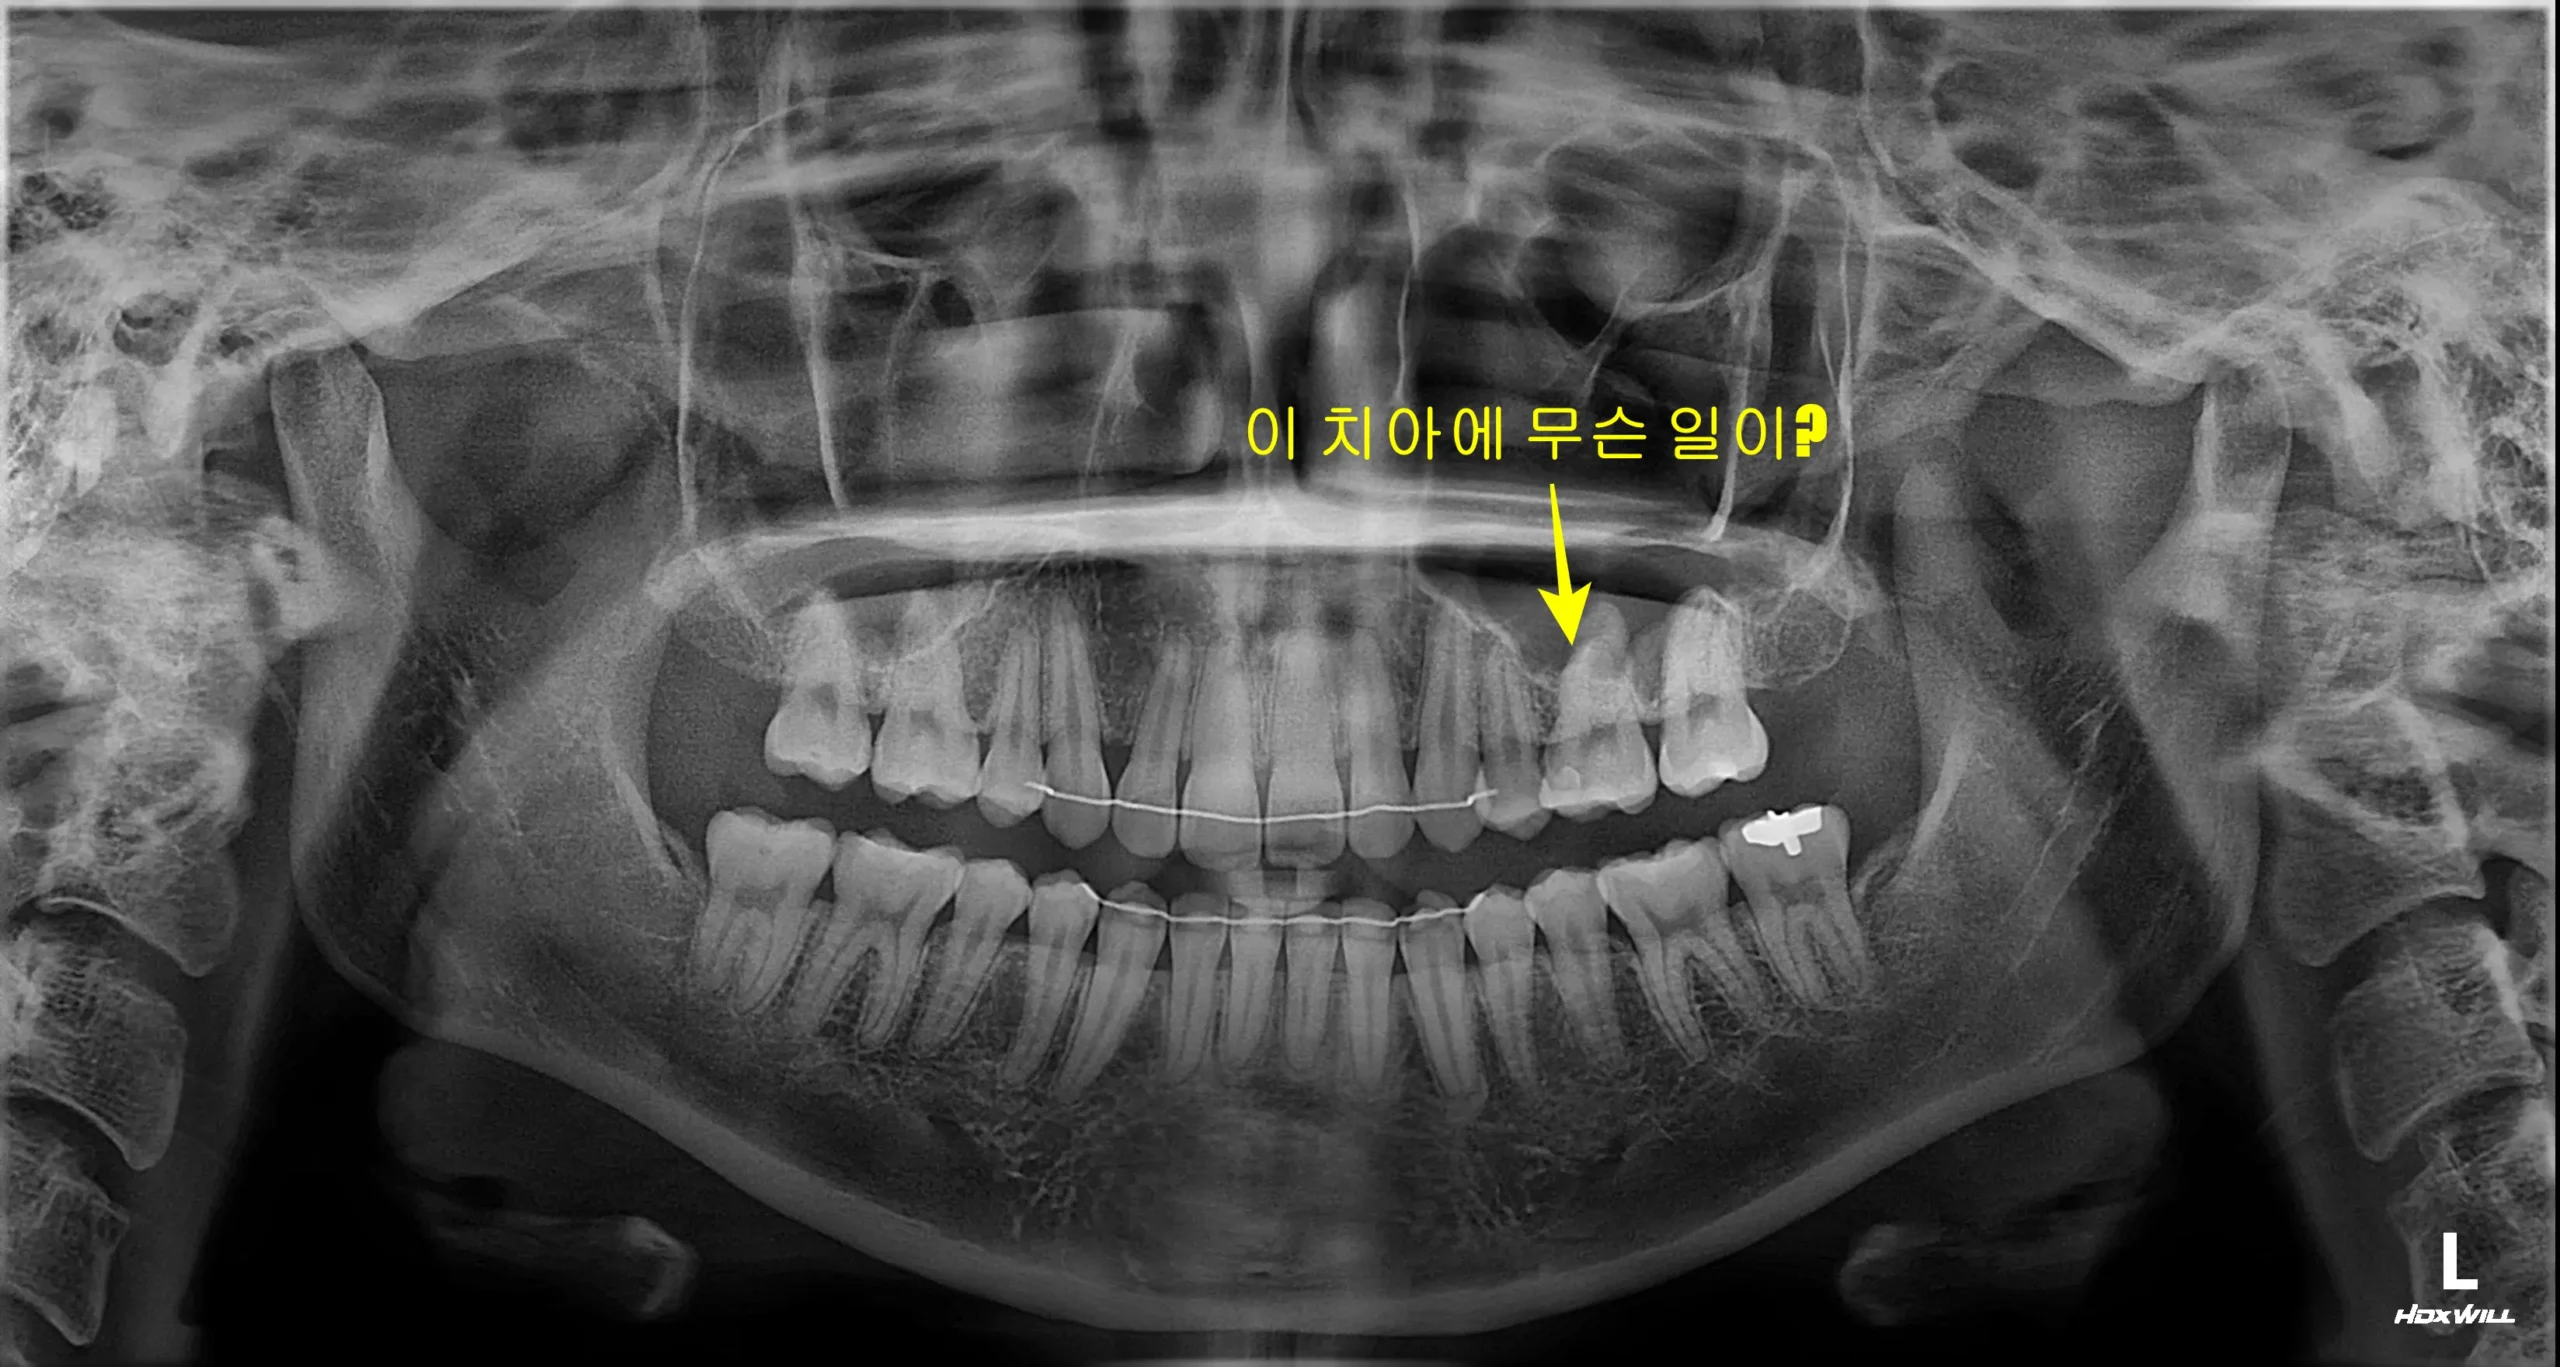

금 간 어금니 꼭 발치해야 할까? 신경치료와 크라운으로 보존하는 기준

신경치료와 지르코니아 크라운 후 9개월 경과를 확인한 파노라마 엑스레이

씹을 때 찌릿하고 찬 것에 예민하면 신경치료 후 크라운 치료를 고려합니다.